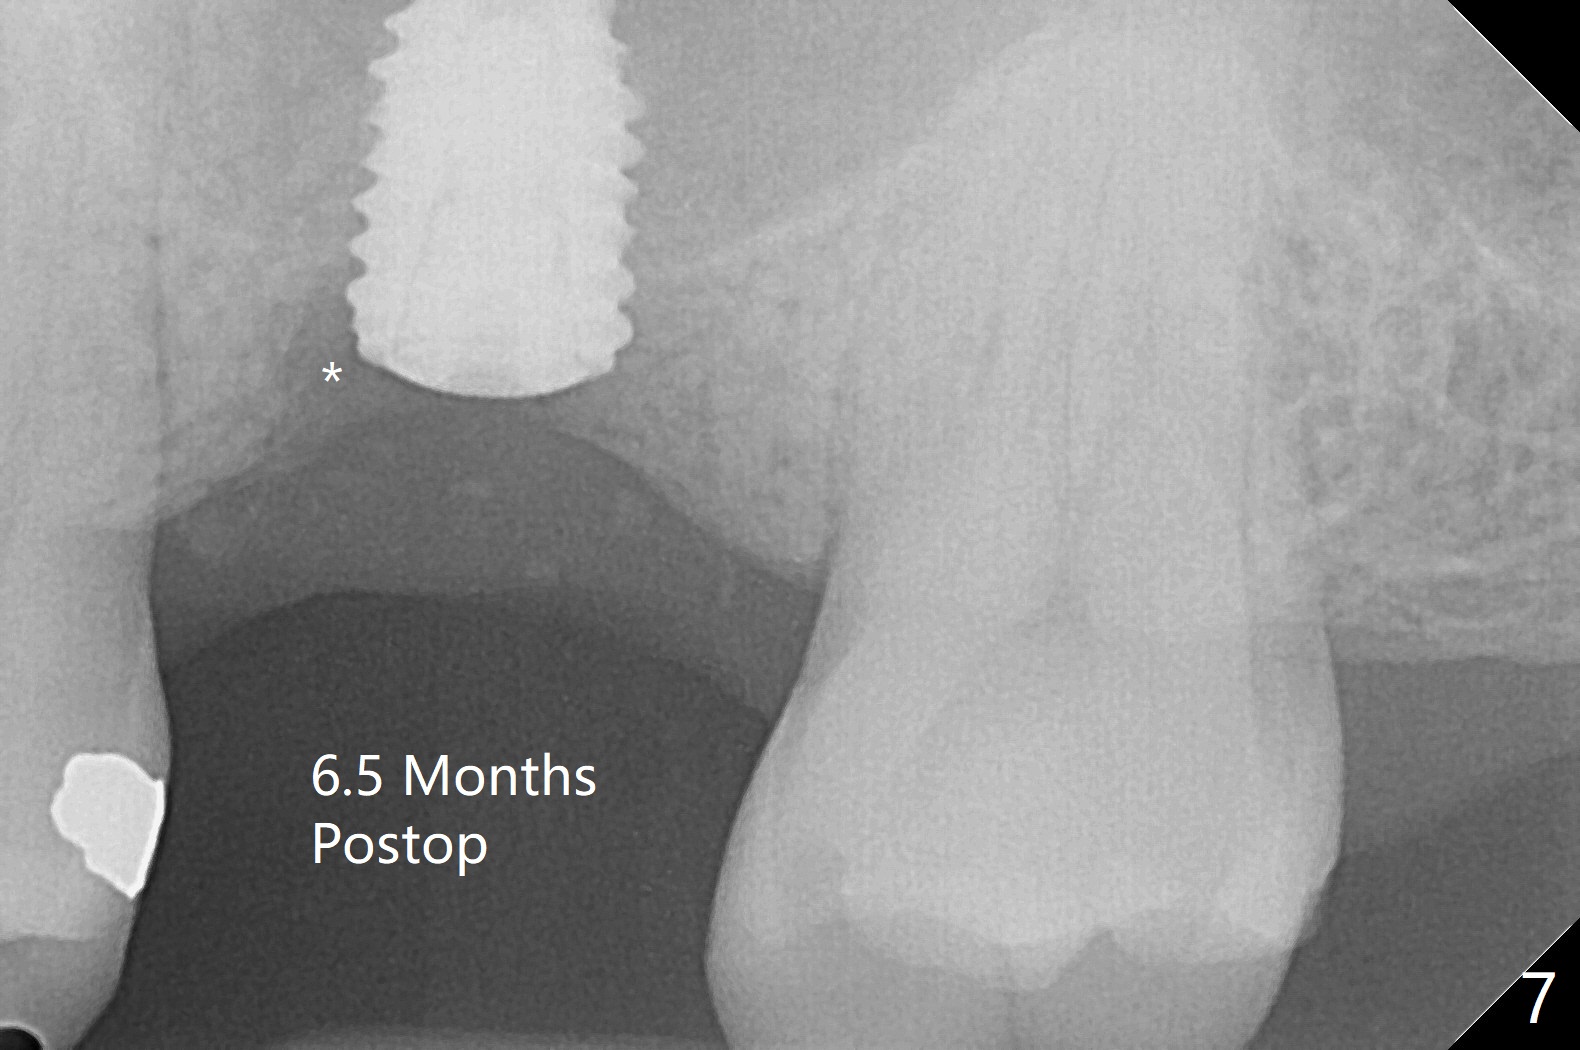

After using 4.5x5.3 mm and 3.5x7.3 mm drill at #14 with guide, the sinus floor is not perforated. When a 4.5x11 mm dummy implant is placed to the 2nd line (12 mm offset), the sinus membrane is perforated (Fig.1). A piece of PRF membrane and sticky bone are pushed into the sinus in an attempt for repair. A shorter implant is placed (5x7.3 (instead of 8.5) mm, Fig.2,3,5, as compared to Fig.3) to reduce postop sinus infection. In fact incision reveals palatal bony concavity. When the implant is placed, there is mild palatal thread exposure. With incision instead of tissue punch, it is easy to place bone graft over the small defect (Fig.3 *). The wound dehisces and heals 2 weeks postop (Fig.6). There is bone loss 6.5 months postop (Fig.7 *), corresponding to palatal thread exposure. After decortication and periosteal underscoring, cortical allograft mixed with ~.25 cc GEM21S is placed (Fig.8 *).